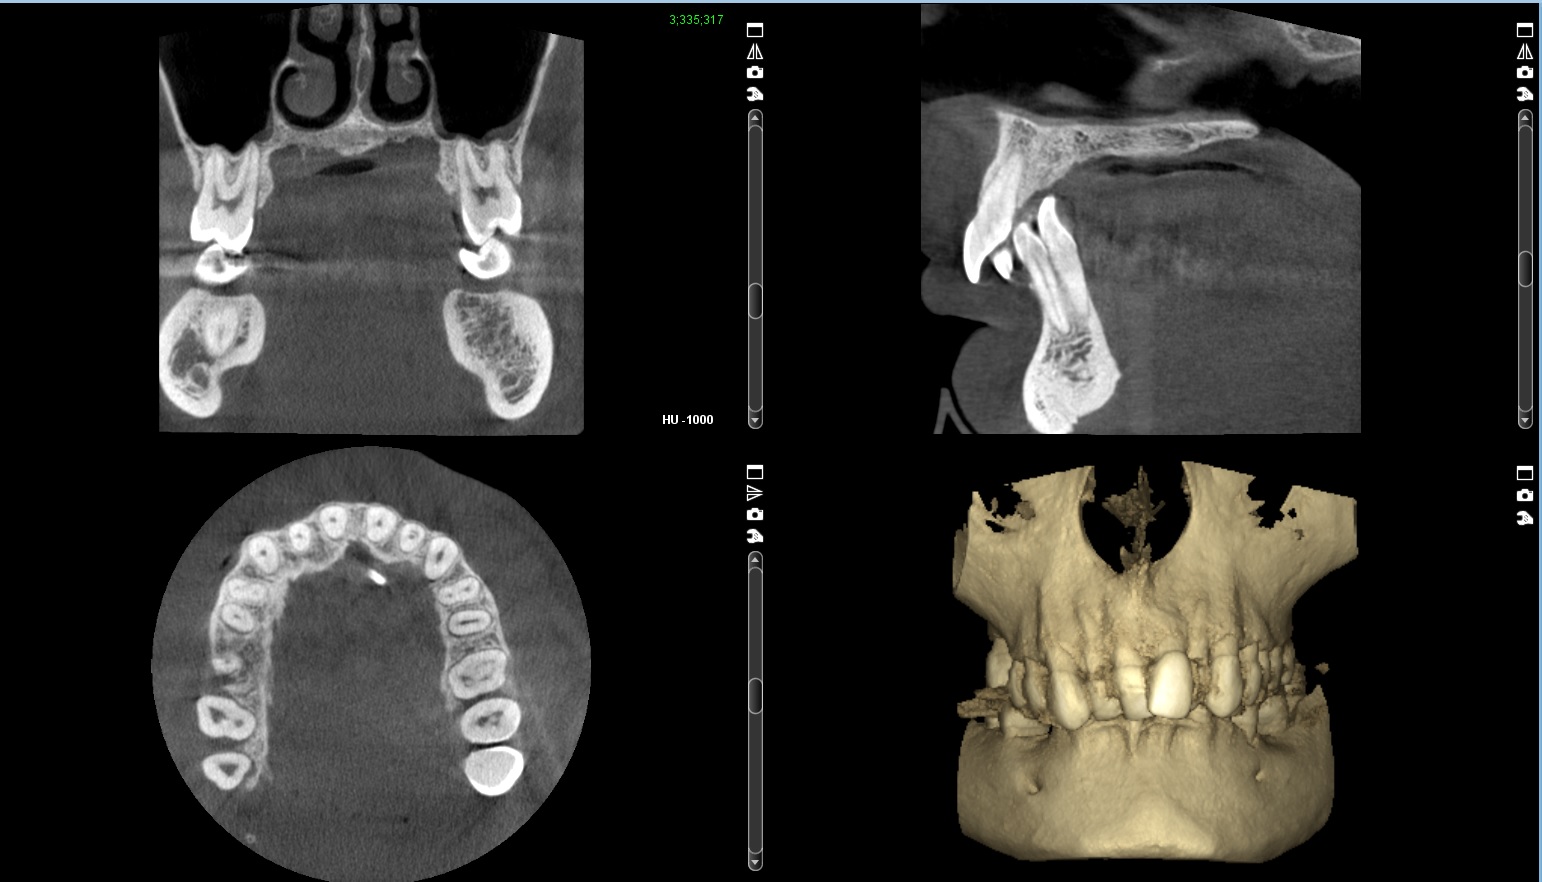

A radiology report can be provided with Fusion Radiology whether a CBCT scan or OPG x-ray. Our radiologist will review the DICOM file from your patient's CBCT scan, interpret the radiographs and create a comprehensive report covering the area of interest and pathology. All of our radiology reports are all in digital format, which will enable you to instantly download a PDF version.